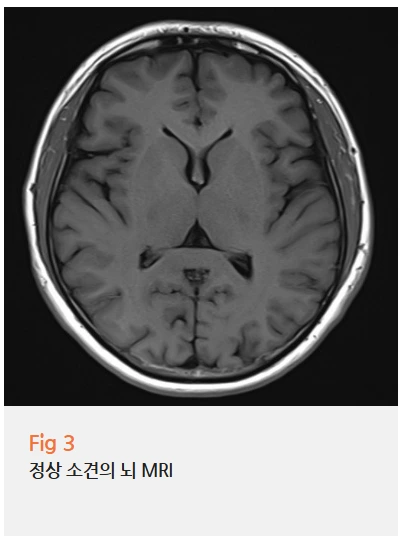

일단 당일 MRI 촬영을 해봤는데요.

요추 4-5번에 디스크 탈출증이 있고,

경추에도 팽윤 디스크가 확인됐어요.

환자분은 허리 통증이나 다리 저림보다는

눈 침침함이나 어지럼증이 주된 증상이라고 생각하셨는데,

알고 보니 목과 허리 디스크가 함께 있는 상태였던 거죠.

특히 경추 디스크는 단순히 목만 아픈 게 아니라 눈어지러움,

시야 흐림, 두통 같은 증상들을 유발할 수 있어요.

왜냐하면 경추 주변에는 자율신경들이 지나가거든요.

이 신경들이 압박받거나 자극받으면

자율신경계 이상 증상이 나타날 수 있는 거예요.